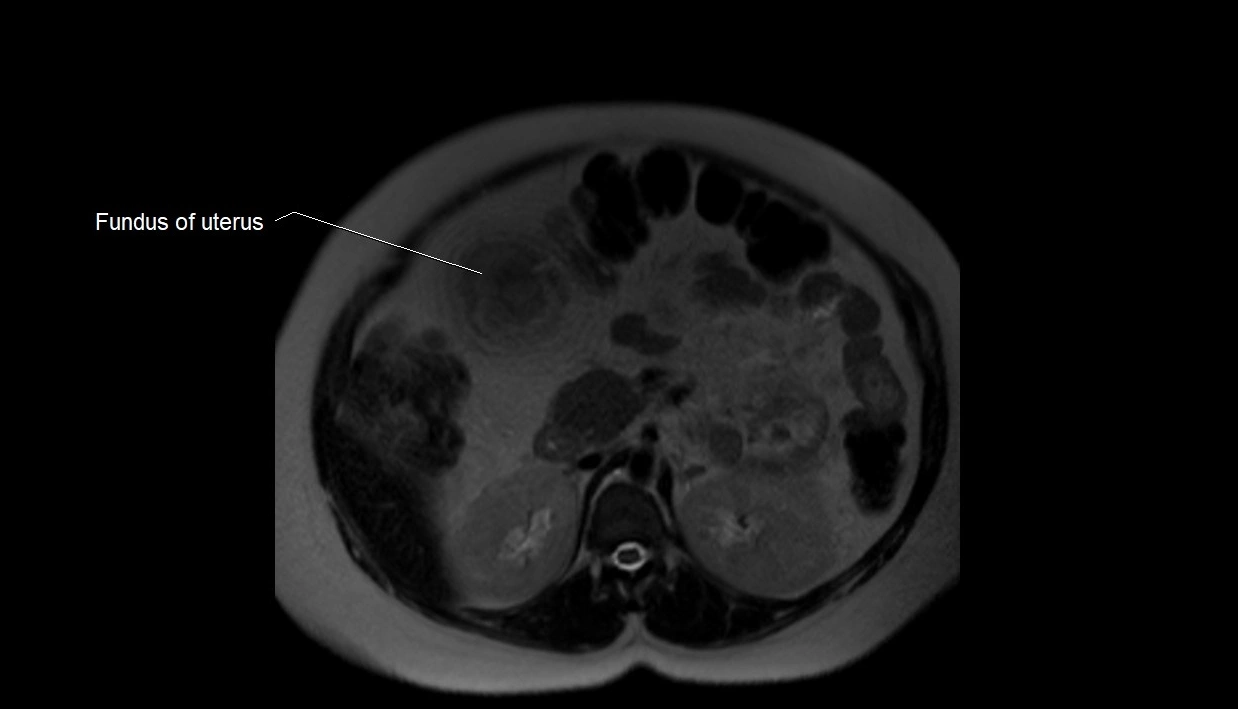

MRI Appearance

T2 HASTE (T2 GRE):

• Amniotic fluid shows very bright hyperintense signal

• Provides natural contrast against fetus and placenta

• Small particles (vernix) may appear as scattered hypointense foci within bright fluid